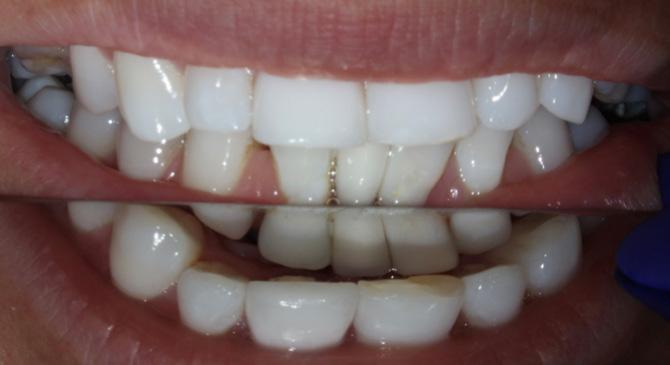

Case 2 – Interdisciplinary Management Following Dental Trauma

A 32-year-old female (Ms A. H.) presented for pre-orthodontic endodontic review following a history of childhood dental trauma. Tooth 41 had been lost previously and replaced with a resin-bonded cantilever pontic attached to tooth 42. Both teeth 31 and 11 had undergone prior root canal therapy of variable technical quality.

Radiographic and CBCT assessment demonstrated apical resorption and a persistent periapical radiolucency associated with 31, while the obturation appeared short and incomplete. Tooth 11 was adequately filled coronally but not fully captured within the imaging field, limiting apical assessment. Tooth 42, which supports the cantilever pontic, appeared vital radiographically but was deemed at risk because of its restorative loading and previous traumatic history. Tooth 55 showed radiographic features of ankylosis with infraocclusion and indistinct lamina dura continuity, consistent with replacement resorption.

From an orthodontic perspective, the patient displayed a Class I skeletal base, moderate anterior crowding, and a mild midline deviation to the right. The lower anterior region showed an edge-to-edge incisal relationship with minimal overjet and overbite, producing limited

space for alignment. The cantilever pontic replacing 41 restricted space management and blocked symmetrical root positioning. Removal of the pontic prior to active treatment was therefore essential to allow accurate space analysis and proper torque control of 42.

Case 2

Figure 4: Periapical radiograph of teeth 31 and 42 demonstrating a resin-bonded bridge replacing the missing tooth 41.

Figure 7: Clinical photograph showing left posterior occlusal relationship.

Figure 5: clinical photograph showing teeth in MI (maximum intercuspal) position.

Figure 8: Clinical photograph showing right posterior occlusal relationship.

Figure 6: Closer view of anterior dentition in MI occlusion with evidence of deep overbite and increased overjet.

Figure 9: clinical photograph of upper right primary second molar.